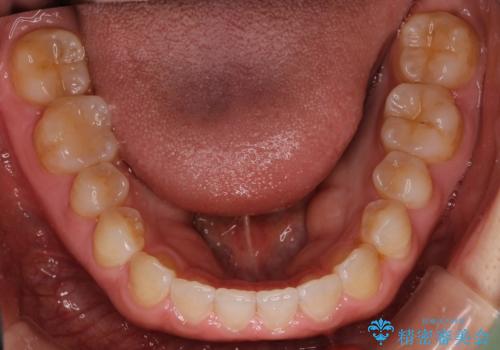

前歯の隙間を閉じたい インビザラインによる矯正

- 上下の前歯に隙間があるとのことで来院されました。

インビザラインにて隙間を閉じる矯正を行いました。

使用時間を守っていただけたので、比較的スムーズに矯正を終了することができました。